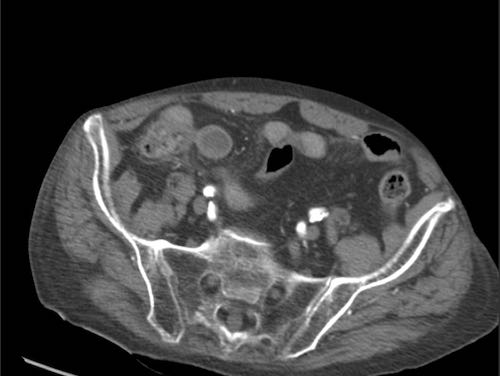

Bệnh nhân nam 85 tuổi này nhập viện với đau khu trú dữ dội, viêm phúc mạc khu trú và CRP 200, lâm sàng nghi ngờ viêm ruột thừa.

Siêu âm cho thấy một vùng nhỏ khu trú gồm mỡ tăng âm bị viêm (đầu mũi tên), chứa một ít dịch (*) và một phản âm khó lý giải (mũi tên trắng).

Chẩn đoán siêu âm dự kiến là viêm phần phụ mạc nối với vùng xuất huyết trung tâm nhỏ.

CT xác nhận thâm nhiễm mỡ khu trú và phát hiện thêm một bóng khí cũng như dày thành nhẹ của một quai ruột non lân cận.

Áp dụng từ gợi nhớ PSI-ABCD, tất cả các nguyên nhân đều được loại trừ, ngoại trừ dị vật sắc nhọn.

Sau khi tìm kiếm có chủ đích, một xương cá được phát hiện tại manh tràng (mũi tên xanh lá trên CT).

Rõ ràng, xương cá này đã gây ra thủng, và sau đó được đẩy đi bởi nội dung ruột non. Bệnh nhân được điều trị bằng kháng sinh đơn thuần và hồi phục hoàn toàn.